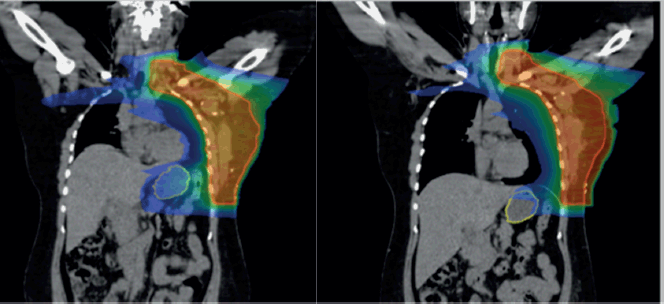

Overall, the significant factors influencing acute upper GI toxicity included radiation technique, RT dose and dose to stomach (D10 cc, D30 cc and D60 cc). Importantly, left chest wall or breast irradiation with or without RNI during FB was associated with a significantly higher risk of GI toxicity compared to DIBH, which holds a significant negative correlation implying a protective effect and helps in reducing GI toxicity (p = 0.035) (Supplementary

Figures 1a,b and 2a,b). Additionally, a positive correlation was found between larger PTV volume and the risk of developing acute upper GI toxicity (p = 0.036).

The Mann-Whitney U test was used to compare stomach dose parameters (D10, D30 and D60 cc) between FB and DIBH. Stomach D10 cc, the higher-dose region most closely associated with acute toxicity, showed no significant difference between FB and DIBH (Mann-Whitney U = 898.500, Z = −1.712, p = 0.087). This suggests that DIBH helps control the dose to critical stomach sub-volumes, potentially reducing the risk of upper GI toxicity. Interestingly, D30 and D60 cc doses were higher in the DIBH group (p = 0.013 and p = 0.002, respectively). However, these differences are likely to reflect anatomical and positional variations associated with breath-hold techniques rather than an increased clinical risk. Clinical correlation with upper GI toxicity indicated a protective trend for DIBH, reinforcing its role in mitigating toxicity by improving treatment reproducibility and reducing motion-related dose variability (Supplementary Figure 2a and b).

Supplementary Figure 1. (a and b): Axial CT scan showing stomach position in FB (VMAT Technique), Figure 3b: showing stomach position in DIBH (VMAT Technique).

Supplementary Figure 2. (a): Coronal view showing stomach position in FB (VMAT), (b): In DIBH (VMAT).